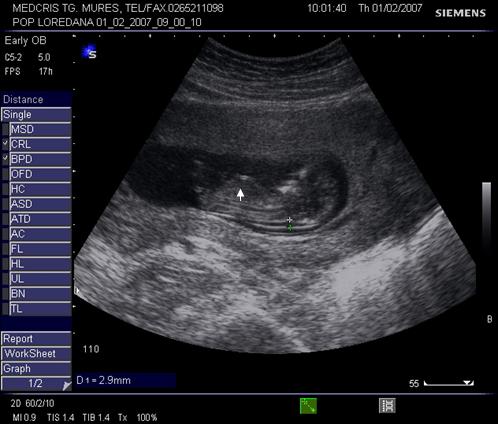

Fig. nr.128 Pliu nuchal cu dimensiunea de 2,9 mm.Cu sageata se remarca alaturat amniosul, magnificatia redusa nu permite obtinerea unei imagini optimale a translucentei nuchale.

Fig. nr.129 Masurarea pliului nuchal la o marire corespunzatoare

Masurarea NT egala sau peste 3 mm este considerata anormala. Riscul defectelor cromozomiale creste marcat in functie de marimea NT si de varsta mamei, necesitand punctie biopsie de vilozitati choriale sau amniocenteza.

Cea mai buna metoda de screening [18] ramane asocierea varstei materne, masurarea translucentei nuchale si nivelul seric matern de HCG β- human chorionic gonadotropin si PAPP-A (Pregnancy associated plasma protein- A) la 11 - 14 sapt gestationale ( dublu test ). Detectarea defectelor cromozomiale este in jur de 90%, cu ajutorul unui soft ce integreaza aceste date si efectueaza calculul riscului relativ.